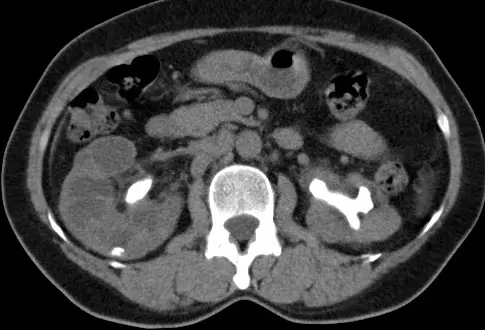

關於下圖之電腦斷層檢查,下列敘述何者最適當?

觀察提供的腹部軸切面(Axial view)電腦斷層影像,可發現以下幾個關鍵特徵:

- 血管與器官無顯影特徵:位於脊椎前方的腹主動脈(Abdominal aorta)與下腔靜脈(IVC)呈現暗灰色的軟組織密度,與兩側的腰大肌(Psoas muscle)密度相仿。同時,兩側腎臟實質(Renal parenchyma)也沒有因顯影劑灌流而出現亮度提升或皮質髓質分界(Corticomedullary differentiation)。

- 極高密度的病灶:在雙側腎臟的中央集尿系統(腎盂與腎萼)位置,可見到極高密度(呈現亮白色,CT 值接近周邊脊椎骨)的結構。

- 病灶形態:這些高密度物質順著腎盂與腎萼的解剖空間生長,呈現向外分支的鑄型外觀,這是非常典型的**雙側鹿角狀結石(Bilateral staghorn calculi)**特徵。

- (A) 此圖為施打顯影劑後之電腦斷層影像,顯影劑已進入腎臟集尿系統:錯誤。若為打藥後的「排泄相 / 延遲相(Excretory / Delayed phase)」,顯影劑確實會聚集於集尿系統使其呈現亮白色